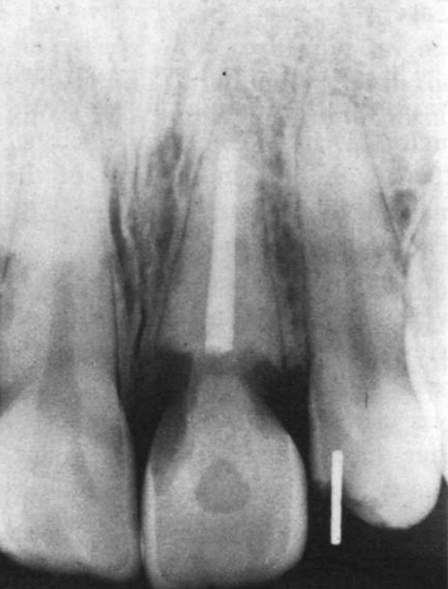

Рентгенограмма, сделанная в то время (через семь лет после завершения эндодонтического лечения), не выявила признаков резорбции коронковой части или корня (рис. 4).

Рис. 4. - Клинический случай 2. Рентгенограмма верхней челюсти до отбеливания, левый центральный резец, в 1967. Эндодонтическое лечение было завершено в 1960 году.